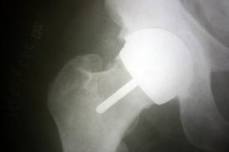

I had a BHR resurfacing in 2004 on my right hip. 5 months ago I had a total hip replacement on my left hip, the surgeon who did this op flagged up on seeing my Xrays that I had a problem with my right hip, I was referred back to the surgeon who did the resurfacing in 2004, I had a CT Scan and blood test, that showed I had that I had all these problems associated with the metal on metal hip, he has now replaced this with a total hip replacement, I am now recovering from two hip replacements in five months.these hips was done through the NHS but at a private hospital, at the horder centre Crowborough.